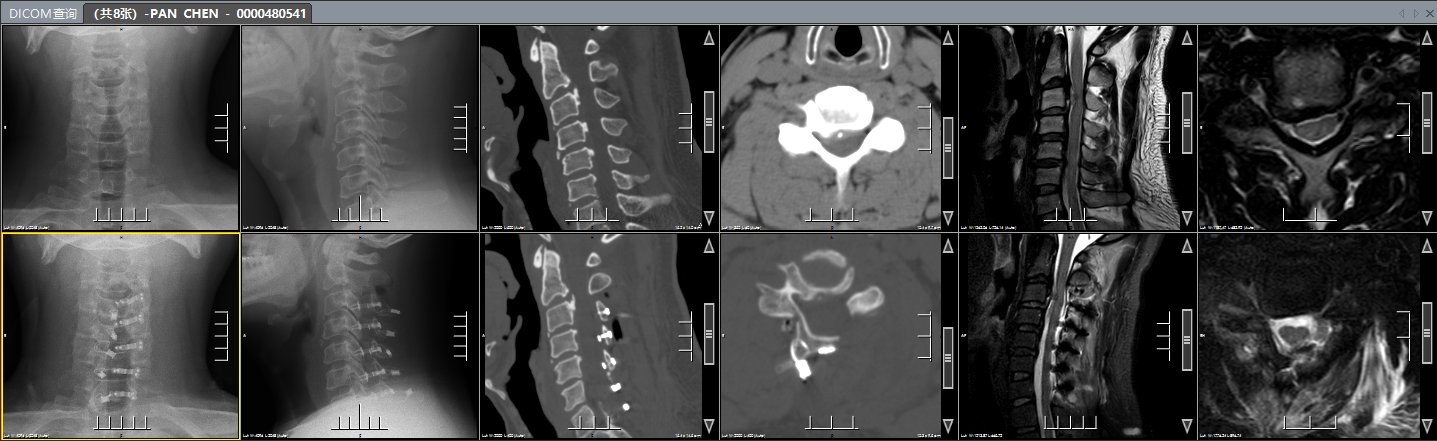

改良颈椎后路单开门手术(保留一侧肌肉韧带复合体)

该手术在术中能够充分减压并解除脊髓压迫,且稳定性强,能够维持颈椎活动度,因此患者在术后能够早期进行功能锻炼,达到有效减少术后并发症的目的,同时该手术可明显改善多节段脊髓型颈椎病患者的神经功能,手术操作简单,临床疗效满意。